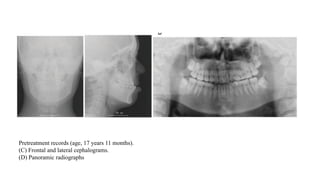

Pretreatment records

(age, 17 years 11 months).

(A) Facial photographs.

Pretreatment records (age, 17 years 11 months).

(C) Frontal and lateral cephalograms.

(D) Panoramic radiographs